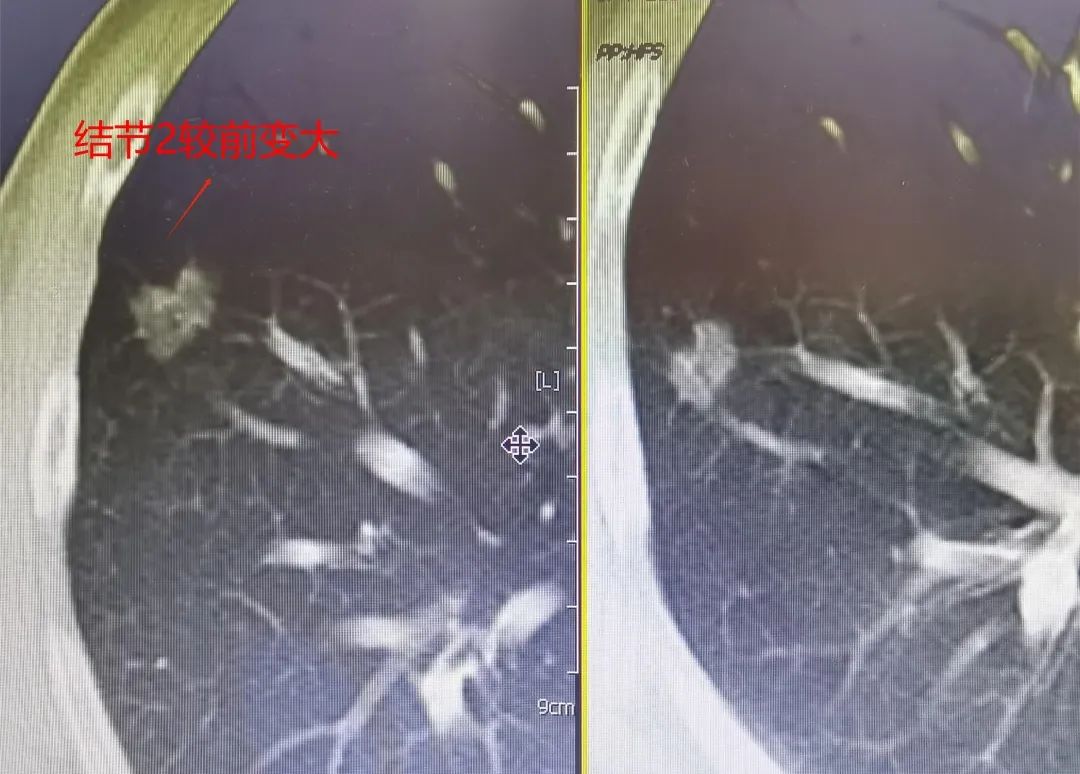

黃大爺5年前經(jīng)我院確診并行賁門癌手術(shù),手術(shù)順利。當(dāng)時(shí),手術(shù)前檢查就發(fā)現(xiàn)了右上肺及右下肺均有一例小結(jié)節(jié),影像檢查排除癌轉(zhuǎn)移,囑患者定期隨訪。今年,接受胸部CT檢查時(shí)發(fā)現(xiàn)兩枚結(jié)節(jié)均較2年前明顯增大、變實(shí),右上肺結(jié)節(jié)約1.2×1.9cm、右下肺結(jié)節(jié)約1.1×1.7cm,影像學(xué)表現(xiàn)高度考慮惡性。

CT影像對(duì)比